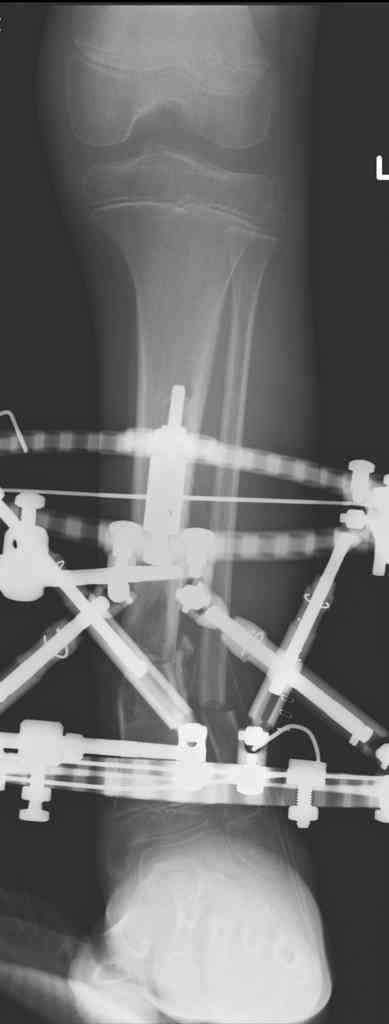

Another choice is simply perform shortening + posterior angulation with Ilizarov or TSF , than gradual correction of the angulation.After all apply third ring on the proximal tibia and start lengthening.

We had recently similar case in 14 years old boy with 45 mm bone defect after open tibial fracture.Boy doing excellent .This technique is not new, Sasha Lerner did it in Rambam , Rozbruch wrote also.

Another advantage of this techniqe is relaxation of soft tissue and possibility for closure even large defects of the skin.In your case I will apply ring on the foot and mid diaphysis of the tibia ,removal of the fibular plate,sindesmotic wire, and after correction of angulation on the proximal tibia.

Да, надо удалить все железо, сделать для ангуляции остеотомию малоберцовой на уровне дефеормации, а после восстановления оси сразу освободить стопу. То есть в дистальном отломке tibia надо побольше

спиц с упорами, а на диафизе только half-pins с передне-внутренней стороны, чтобы как можно меньше пострадала передняя группа мышц.

Temporary Intentional Leg Shortening and Deformation to Facilitate Wound Closure Using the Ilizarov/Taylor Spatial Frame Shane J. Nho, MD, David L. Helfet, MD, and S. Robert Rozbruch, MD (PDF, 474 Kb)